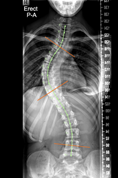

Scoliosis AI

Automatic measurement of spine curves. Limited generalizability.

A. Ha, B. Do, et al.

Skeletal Maturity

Skeletal Maturity Extraction

Automatic Extraction of Skeletal Maturity from Whole Body Pediatric Scoliosis X-rays.

Audrey Ha, John Vorhies, et al.